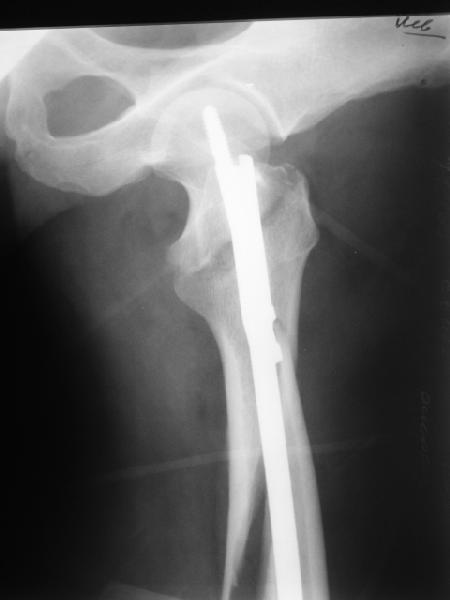

В диагноз пишем... Потом же как-то анализировать надо. Что-то никто не откликнулся на этот вопрос из англоязычных коллег. Все-таки - как такой перелом надо классифицировать? А если шейка бедра + диафиз? Завтра покажу такой случай.

Реконструкционный гвоздь.

Да, сейчас это и у нас самый напрашивающийся выбор. Сделали гвоздем ChM, картинки в приложении.